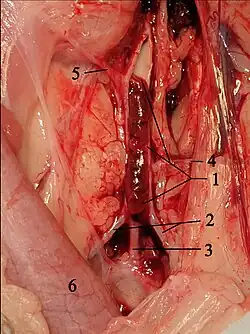

In cats, the blood clots originate mainly in the left atrial auricle.[8] They or parts of them are carried along with the blood flow, enter the aorta via the left ventricle, get stuck at vascular outlets and block them. This condition is called thromboembolism. In cats, this occurs predominantly in the aorta in the area of its terminal branch, i.e., at the outlet of the two external iliac arteries (Aa. iliacae externae). This is also called "saddle thrombus" or "riding thrombus". This results in an ischemia to the rear extremities. In addition, platelets release thromboxane and serotonin, which leads to vasoconstriction and thus to reduced blood flow even to blood vessels that are not directly affected. Serotonin also stimulates nociceptor, which contributes to the high painfulness of the disease.[9] Only in 10% of cases are other blood vessels affected, for example the brachial artery, pulmonary arteries, cerebral circulation, intestinal vessels or coronary arteries.[10][11]

Listening to the heart (auscultation) usually reveals heart murmurs, an irregular heartbeat, palpitations, extrasystoles and a "gallop rhythm" - a sequence of heart sounds reminiscent of a galloping horse. Up to two-thirds of FATE patients are in congestive heart failure,[9] in which the heart no longer pumps enough blood to the body. Atrial fibrillation detectable by ECG is an additional risk factor. Aortic thrombus can often be visualized directly by sonography,[26] and angiography or electromyography may also be performed if necessary. Echocardiography can be used to visualize thrombi and their precursors in the heart and to assess the functional status of the heart. Loss of pulse at the femoral artery can also be detected by doppler sonography, although the pulse is still detectable sonographically if the vessel is incompletely occluded.[27] Infrared thermography can be used to objectify temperature differences between the forelimbs and hindlimbs. The sensitivity of this method is between 80 and 90 %, the specificity is 100 %.[28] A thromboembolism of the lung often remains undetected; in this case, a chest radiograph can provide initial indications, and a definite diagnosis can be made by means of CT scan[21] or scintigraphy of the lung.[29] If a stroke is suspected, magnetic resonance imaging is indicated.[22]